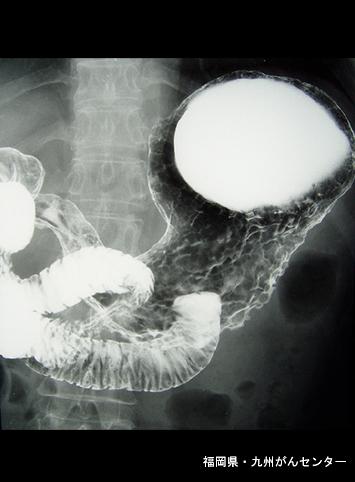

Posted by: Fukuoka Pref., National Hospital Organization Kyushu Cancer Center

Criteria of Hist.ClassificationMalignant epithelial tumor/Adenocarcinoma

LocationStomach/More than one of above

Technique, MethodX-ray

Macroscopic TypesType 4 Diffusely infiltrating type/

Size40 -

Depth of Tumor Invasionsubserosa (subadventitia)